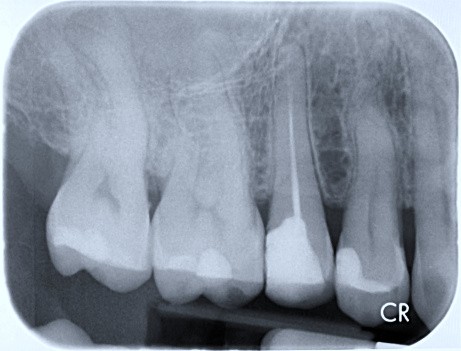

The radiograph shows evidence of

The radiograph shows evidence of calculus on